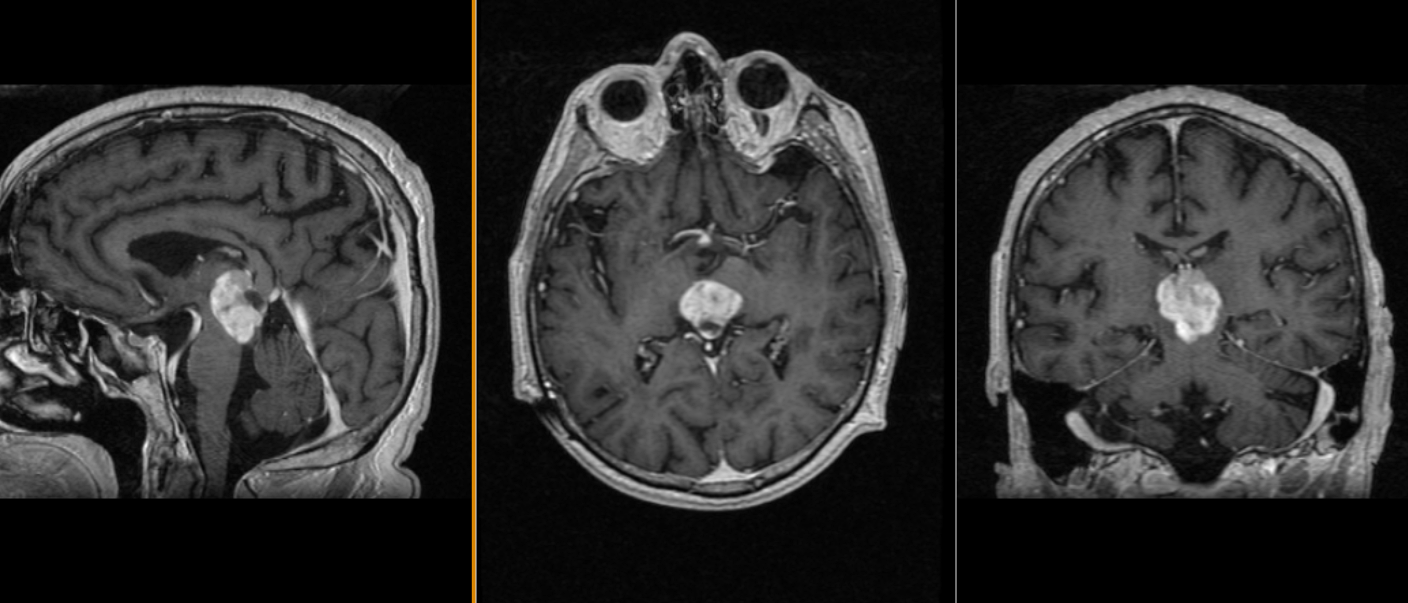

Mică tumoră de glandă pineală – pinealocitom